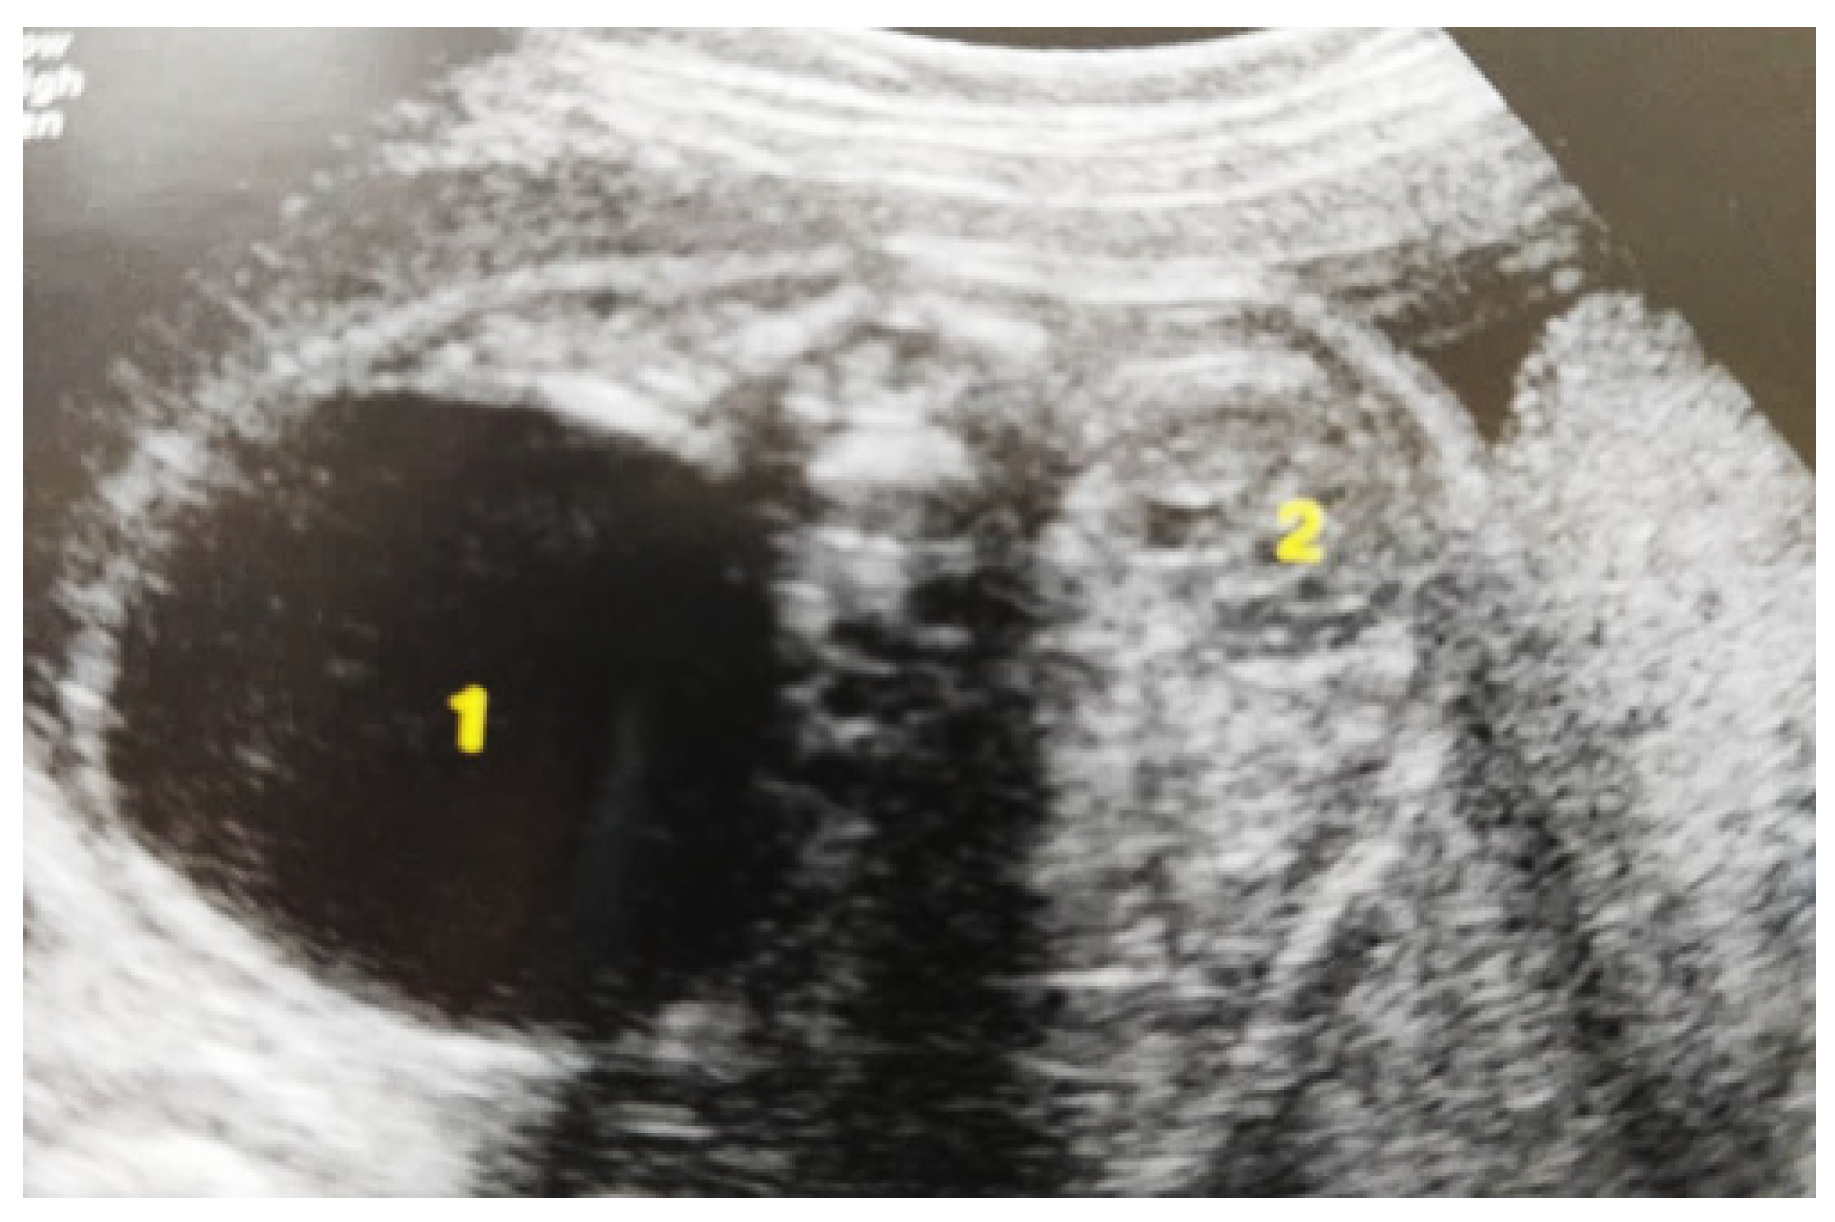

Figure 3. Ultrasound at the 20th week of gestation. Hydronephrosis on the right. (1) Dilated pelvis on the right. (2) Uninjured renal parenchyma on the left.

Our experience with congenital malformations of the urinary system refers to the following clinical case (Figure 2, Figure 3, Figure 4, Figure 5, Figure 6, Figure 7, Figure 8 and Figure 9). In the first case, during pregnancy, the 21-week ultrasound determined bilateral renal pyelectasia. The fetus had hydronephrosis on the right; at 31 weeks, it had bilateral hydrocalconephrosis; and at 32 weeks, bilateral pyelectasia. It suffered premature birth at 36 weeks, with complicated anomalies of the forces of contraction, prolonged birth, and birth weight of 2200 g. Postnatal ultrasonography was supplemented by intravenous urography, and bilateral hydronephrosis was determined. Hydrocalconephrosis on the left was discovered. The complete diagnosis was established: congenital renal malformation; bilateral pyelectasia; bilateral hydronephrosis; hydrocalconephrosis on the left; and severe reduced glomerular filtration rate (GFR), GFR > 2SD below mean.